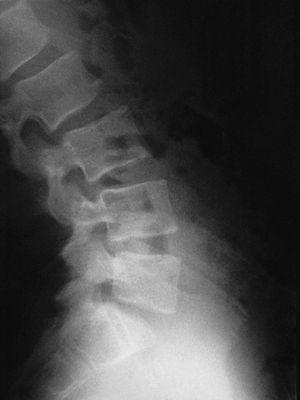

En la visita següent el pacient es presenta amb radiografies que confirmen el diagnòstic d'espondilòlisi L5 unilateral dreta (figs. 1 i 2). D'acord amb el document de consens de la Societat Catalana de Medicina de l'Esport, se sol·licita una gammagrafia òssia planar (GOP) amb tomografia computaritzada per emissió de fotó simple (SPECT). Es decideix continuar amb el mateix tractament i s'assabenta el pacient que serà un tractament a llarg termini.

Figura 2

El nou estudi radiogràfic demostra espondilòlisi L5 dreta i persistència d'integritat de l'hemiarc esquerre (figs. 5 i 6). Igualment, l'estudi radiogràfic dinàmic demostra estabilitat completa de l'articulació lumbosacra (fig. 7). Per tot això es planteja l'alta esportiva, per bé que es recomana de continuar un mes més el tractament, i ajornar la tornada a la pràctica esportiva.

Figura 5

Figura 6